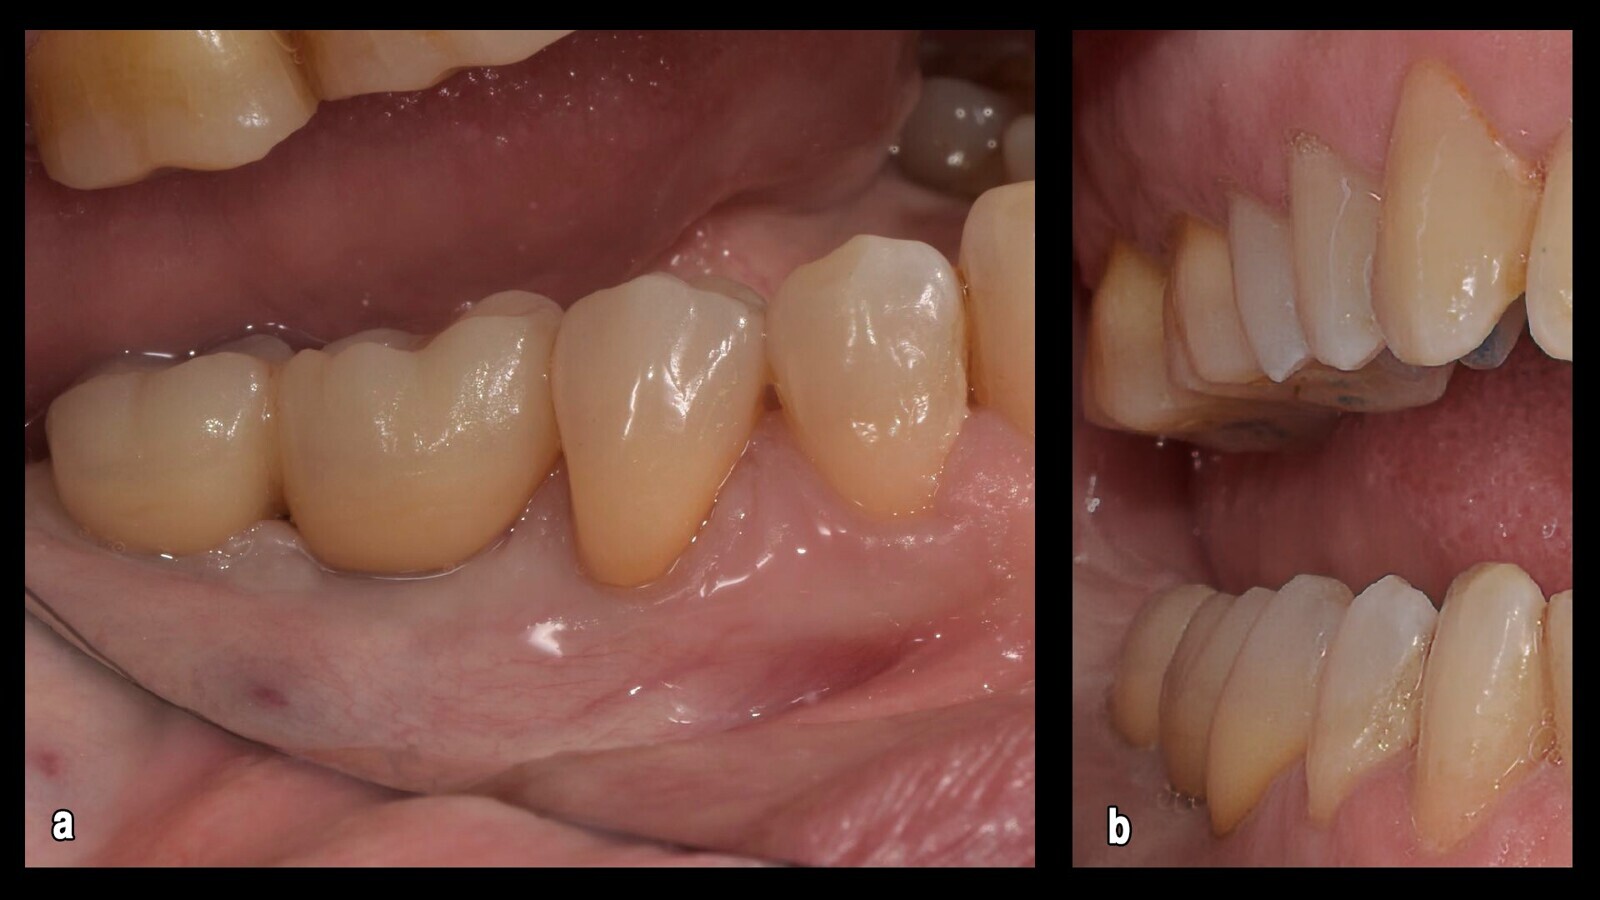

Figura 1. El examen intraoral mostró que los túneles gingivales estaban completamente cerrados (a) para la regeneración del tejido (b), confirmando el tiempo transcurrido desde que se desatornillaron.